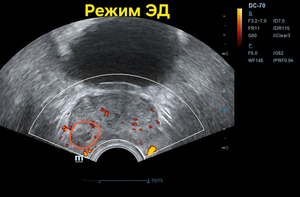

Всё бы ничего, но только на ТРУЗИ объём простаты несколько превышен — 39,6см³, а в периферической зоне справа округлый т. н. атипичный узел диаметром 11,0 мм со слабым кровотоком (фото 1 — 3); а по статистике именно в этой зоне выявляется до 70% рака.

Фото 3 — ТРУЗИ, режим ЭД